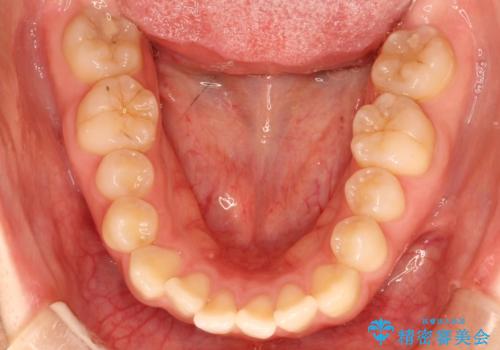

前歯にがたつきがあり、上下の歯が咬み合っていない状態でした。

歯列の横幅をひろげるのと、歯と歯の間をわずかに削ることにより、前歯のがたつきと、開咬を改善しました。